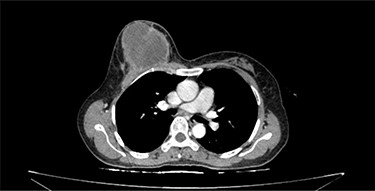

CT scan of the chest revealed a large tumor involved whole right breast tissue (Fig. 1), bilateral pulmonary metastasis without mediastinal adenopathy (Fig. 2) and axillary lymph node enlargement measuring 1.5 cm with central necrosis.